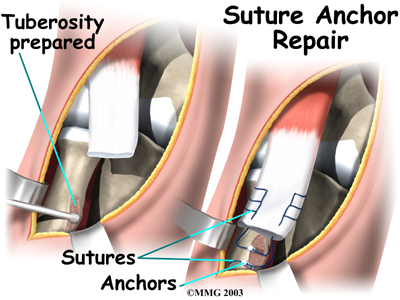

Suture Anchor Method

A new method of anchoring the torn tendon to the radius is gaining popularity. This method uses special anchors, called suture anchors, to fix the tendon in place. The procedure requires only one incision and appears to lessen the risk of myositis ossificans. Myositis ossificans is an abnormal healing response that causes bone to form in the muscles and soft tissues.

A new method of anchoring the torn tendon to the radius is gaining popularity. This method uses special anchors, called suture anchors, to fix the tendon in place. The procedure requires only one incision and appears to lessen the risk of myositis ossificans. Myositis ossificans is an abnormal healing response that causes bone to form in the muscles and soft tissues.

The surgeon begins by making a across the arm, just above the elbow. Along the outside edge of the arm, the incision curves and goes upward for a short distance. The skin and underlying tissues are pulled back using retractors. This reveals the front of the lower biceps muscle and allows the surgeon to avoid injuring nearby nerves and arteries. The fascia (connective covering over the muscle) is cut away so the surgeon can see the radial tuberosity.

The original attachment on the radius, the radial tuberosity, is by shaving off the surface with a burr. The burr is then used to create a small cavity in the bone for the tendon to fit inside. Two small suture anchors are embedded into the cavity in the radial tuberosity. These anchors can either be screwed into the bone or implanted like a staple. Each anchor has a long thread (suture) connected to it. The into the lower end of the tendon and crisscrossed upward. The surgeon slides the sutures back and forth, which coaxes the end of the tendon into the cavity. When the end of the tendon is positioned in the cavity, the surgeon tightens the sutures, fixing the tendon in place.

When the surgeon is satisfied with the repair, the skin incisions are closed, and the elbow is placed either in a cast or a range-of-motion brace.

A new method of anchoring the torn tendon to the radius is gaining popularity. This method uses special anchors, called suture anchors, to fix the tendon in place. The procedure requires only one incision and appears to lessen the risk of myositis ossificans. Myositis ossificans is an abnormal healing response that causes bone to form in the muscles and soft tissues.

A new method of anchoring the torn tendon to the radius is gaining popularity. This method uses special anchors, called suture anchors, to fix the tendon in place. The procedure requires only one incision and appears to lessen the risk of myositis ossificans. Myositis ossificans is an abnormal healing response that causes bone to form in the muscles and soft tissues.